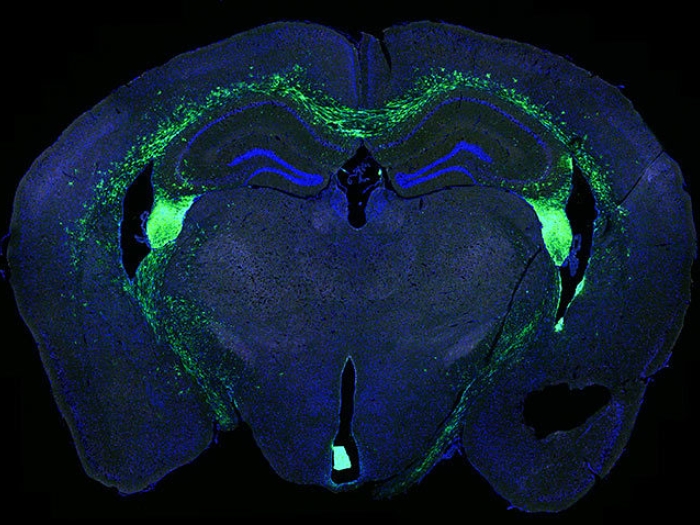

microscopic collagen tumor green blue

Health Lab

Dynamic cells linked to brain tumor growth and recurrence

In mice, researchers have discovered the presence of oncostreams, highly active cells connected to how brain tumors grow and invade healthy tissue.